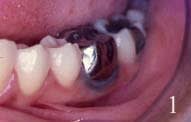

Voici donc 2 diapos :

1-Tatouage après pose d'une couronne Nicr

Le tatouage est dû au passage de l'ion Fe dans la gencive.

A mon humble avis, le tatouage gingival n'étant pas systématique après la pose d'une couronne métallique en Ni-cr, le terrain est patient n'est pas à négliger.

Dans ce cas clinique aucun traitement n'a été effectué malgré les doléances du patient.